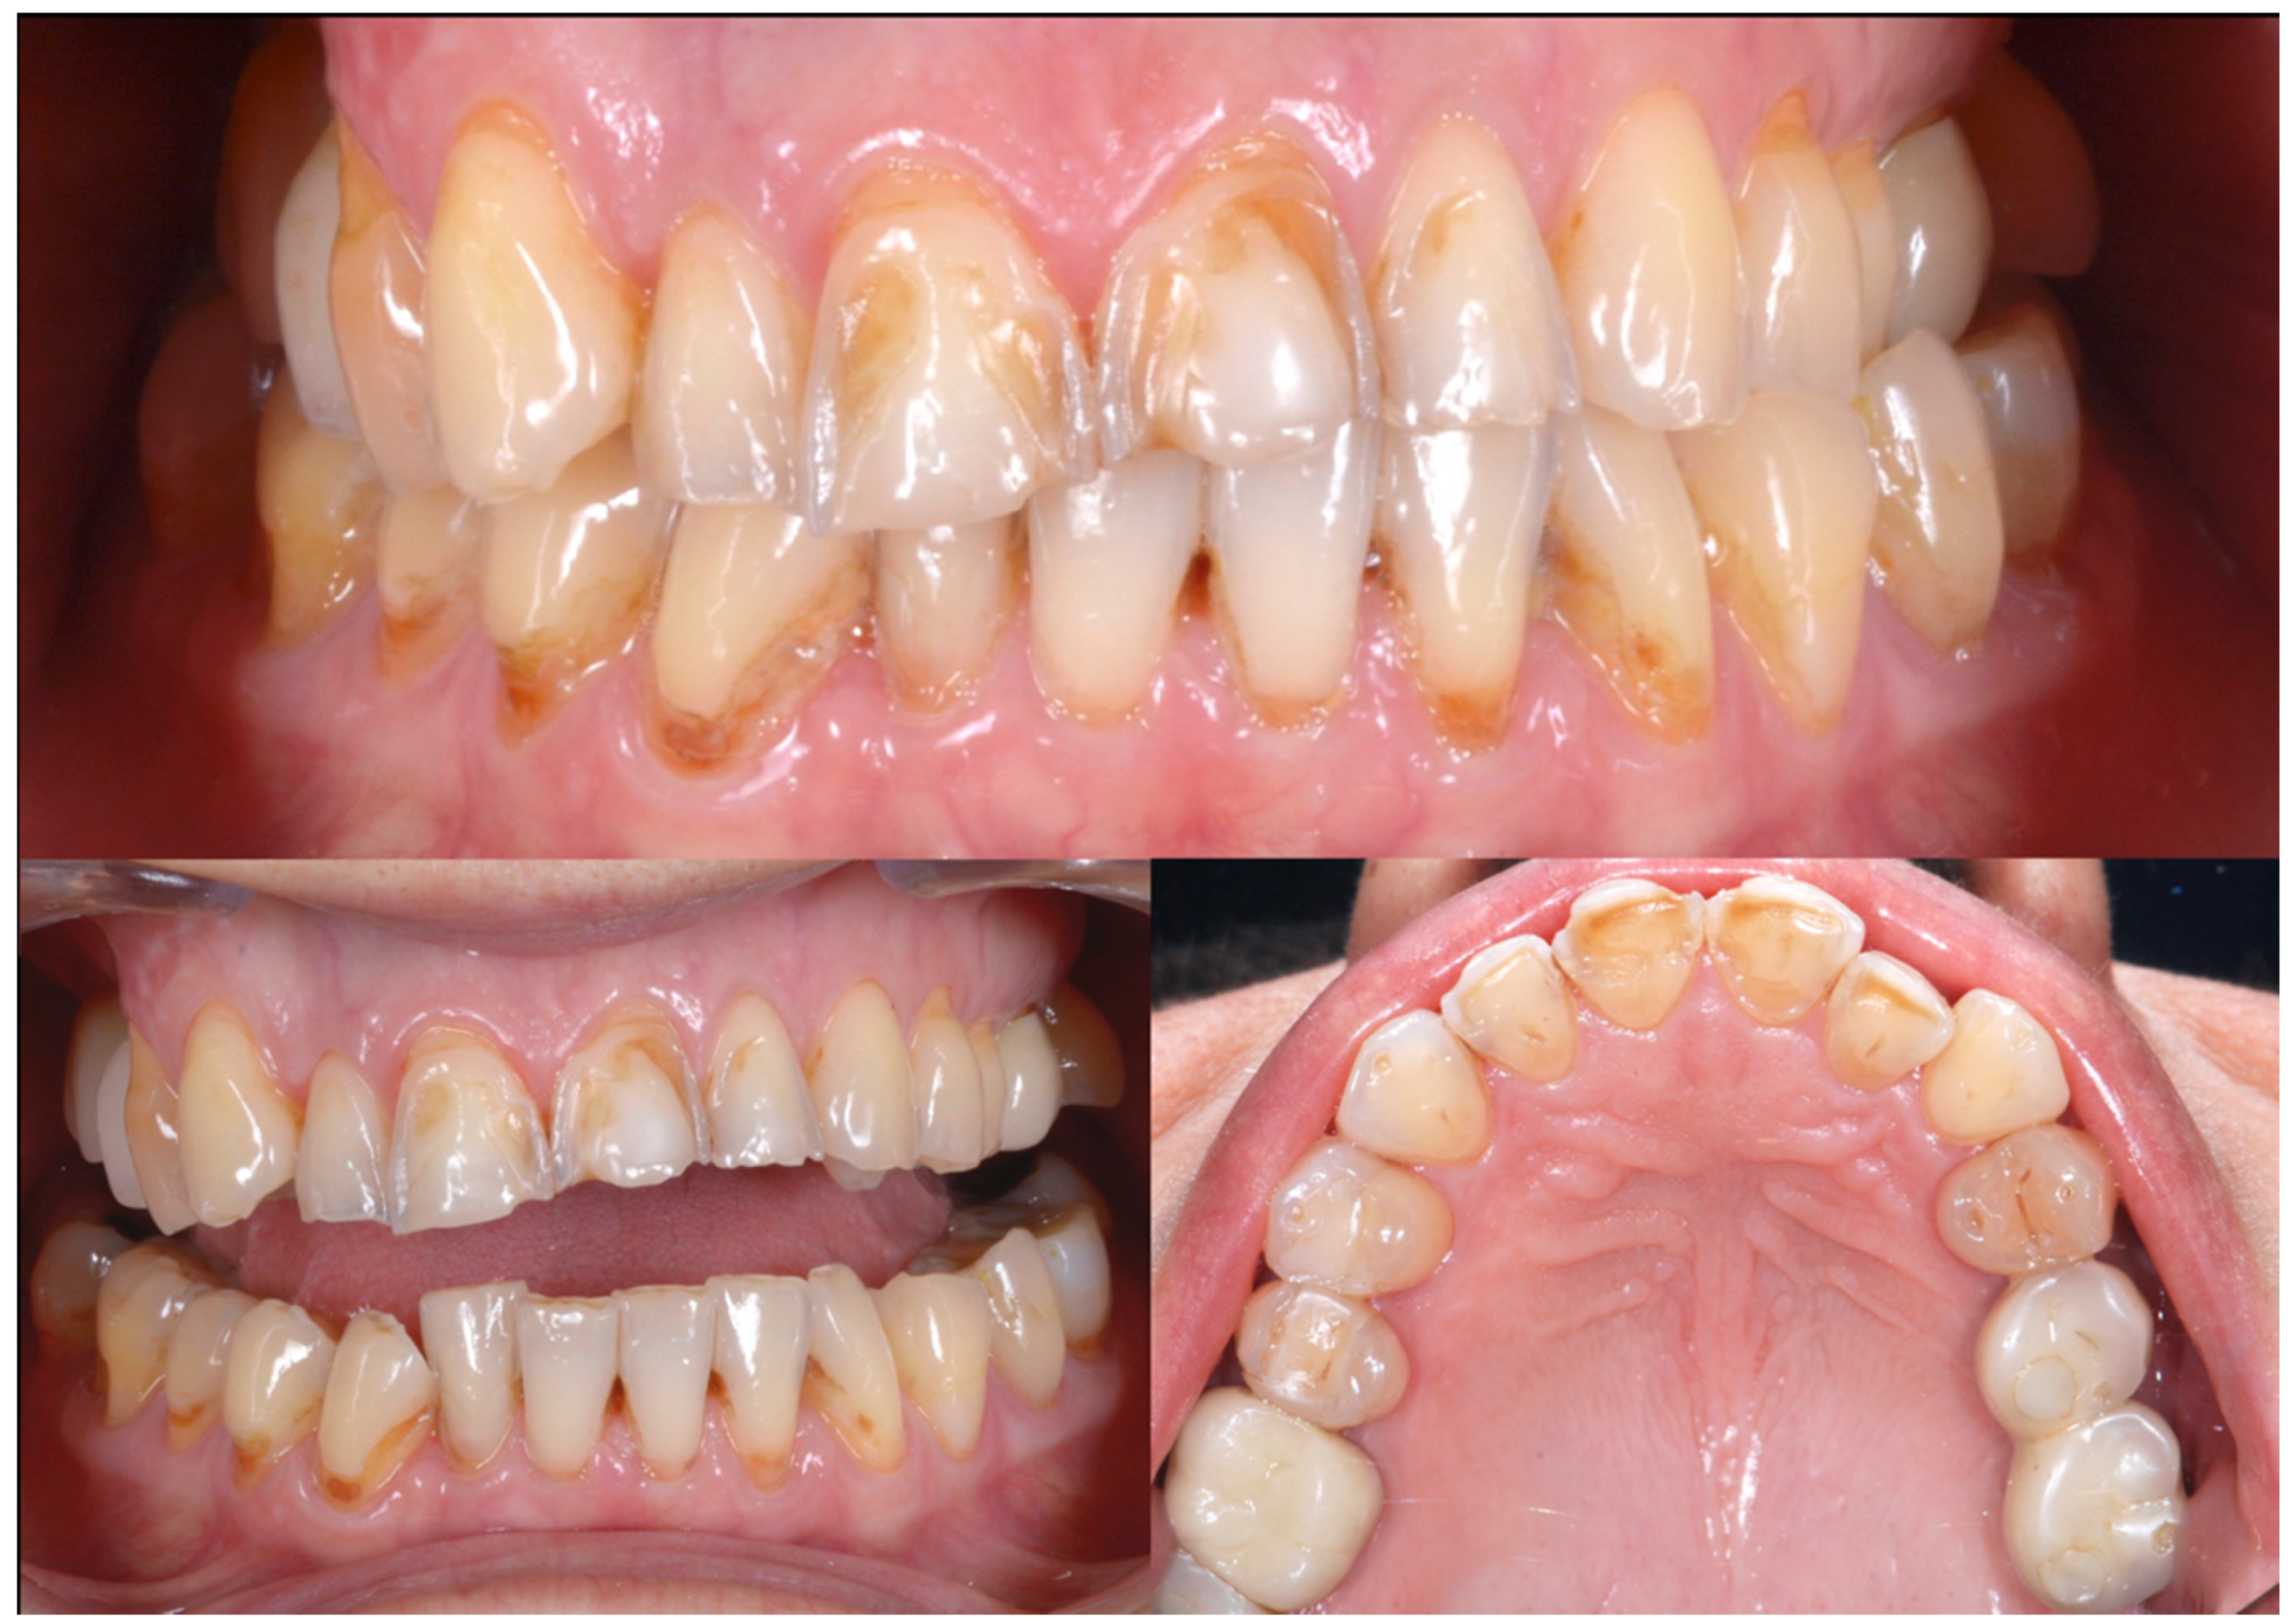

2.2. Clinical Example

2.3. Outcome Achieved